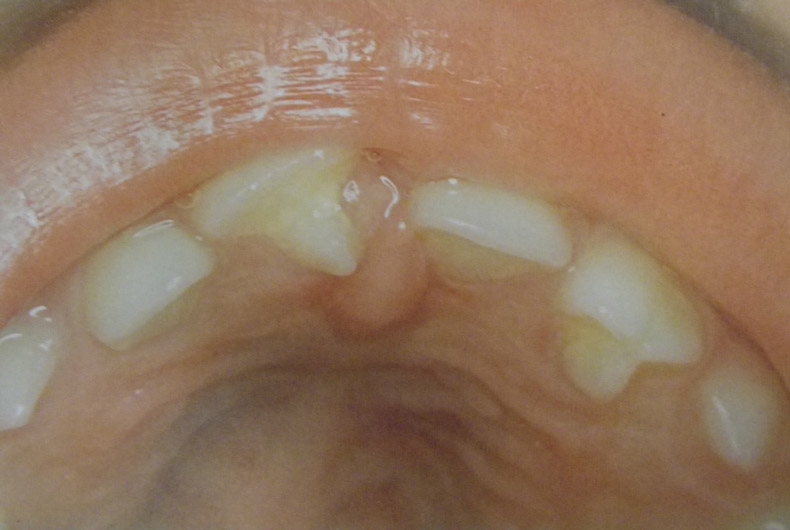

Ανωμαλίες αριθμού, θέσης και σχήματος νεογιλών και μονίμων δοντιών

Υπάρχουν διάφορες καταστάσεις που χρήζουν διάγνωσης και θεραπείας από τον παιδοδοντίατρο. Δείτε τις μία προς μία κάνοντας κλικ στις παρακάτω εικόνες.